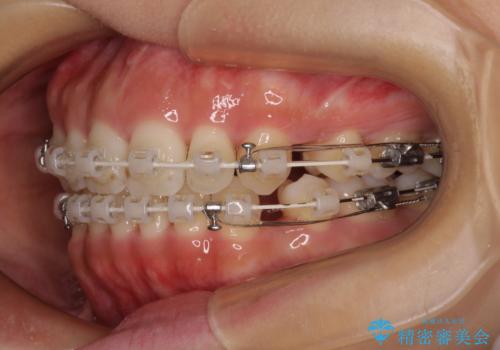

- 審美装置

- 1年8ヶ月

- 上下前歯の隙間と口元の出っ張った感じを気にして来院された患者様です。

上下の隙間は舌突出癖によるもので、またその癖により前歯が前方に出ている状態でした。

口元の出っ張りを改善するため、上下左右第一小臼歯4本を抜去し、ワイヤー装置にて矯正治療を行うこととしました。

舌の突出癖を改善するためのトレーニングをしっかりと行っていただいたことで、比較的スムーズに治療を進めることができました。

口元の突出感もしっかりと改善することができました。